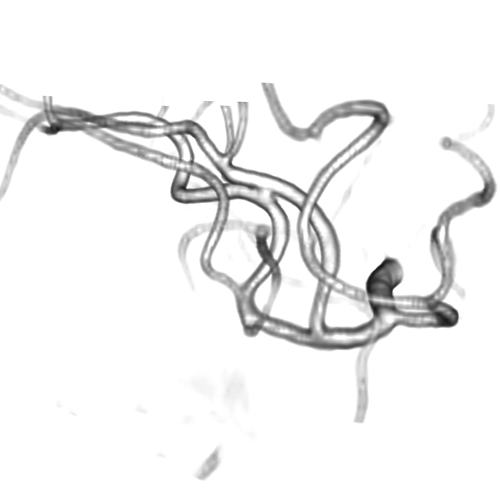

3.1 Connectedness of the Vesselness Map

Fig. 3 shows the connectedness of vessels recovered from state-of-the-art vascular enhancers and curvilinear ridge detectors FFR and OOF together with the proposed CVM for the synthetic HCP and the real PC images.

On the synthetic phantom, FFR shows a fragmented and rough vesselness response in correspondence of irregularly shaped sections of the structure. Also, the response at the bifurcation is not smoothly connected with the branches (triangular loop). Conversely, OOF recovers the phantom connectedness at the branch-point, and the vesselness response is consistent along the tortuous curvilinear section, however ghosting artifacts are observed as the shape of the phantom becomes irregular (C-like) or differs from a cylindrical tube. Also, close convoluted structures, which change scale rapidly in the HCP, produce inconsistent responses of OOF (fig. 3). CVM shows here a strongly connected vesselness response in correspondence of both regular and irregular tubular sections, with local maxima at structures’ mid-line. The connectedness of the structures is emphasized regardless the complexity of the shape, and it resolves spatially the tortuous curvilinear ‘kissing vessels’ without additional ghosting artifacts, despite the smooth profile.

Similar results are observed on the PC dataset: FFR has a poor connected response in the noisy and low-resolution image. Vessels are overall enhanced, however thin and fragmented structures remain disconnected. Overall, the vesselness response is not uniform within the noisy structures, where maximal values are often off-centred. A more consistent response is obtained from OOF, where the connectedness of vessels is improved. Maximal response is observed at the mid-line of vessels, however, noise rejection is poor. CVM strongly enhances here the vessel connectivity. The fragmented vessels of PC have a continuous and smooth response in CVM with higher values and a more defined profile. Large vessels shows solid connected regions with local maxima at mid-line as in OOF. Conversely from OOF, CVM shows improved noise rejection in the background.